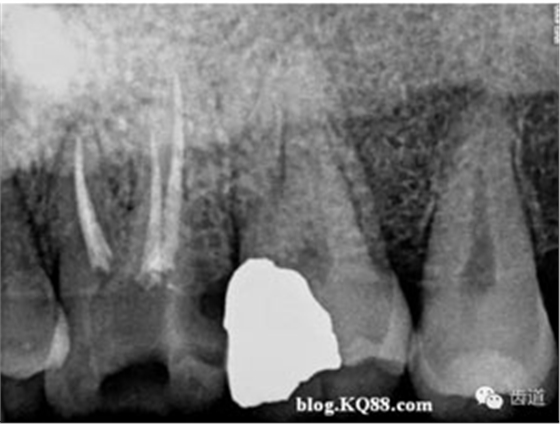

再加熱1秒鐘,停止加熱后迅速帶出距工作長度5mm以上的多余牙膠尖。后用選擇好的垂直加壓器加壓。完成根尖1/3的充填。

開啟熱牙膠注壓充填器,將手柄頭插入根管內(nèi),將尖端頂在充好的根尖 1/3牙膠處,輕按開關(guān),牙膠即可流出。充2-3MM后換合適的垂直加壓器加壓。

重復(fù)上一步驟直到完成根管冠方2/3的充填。